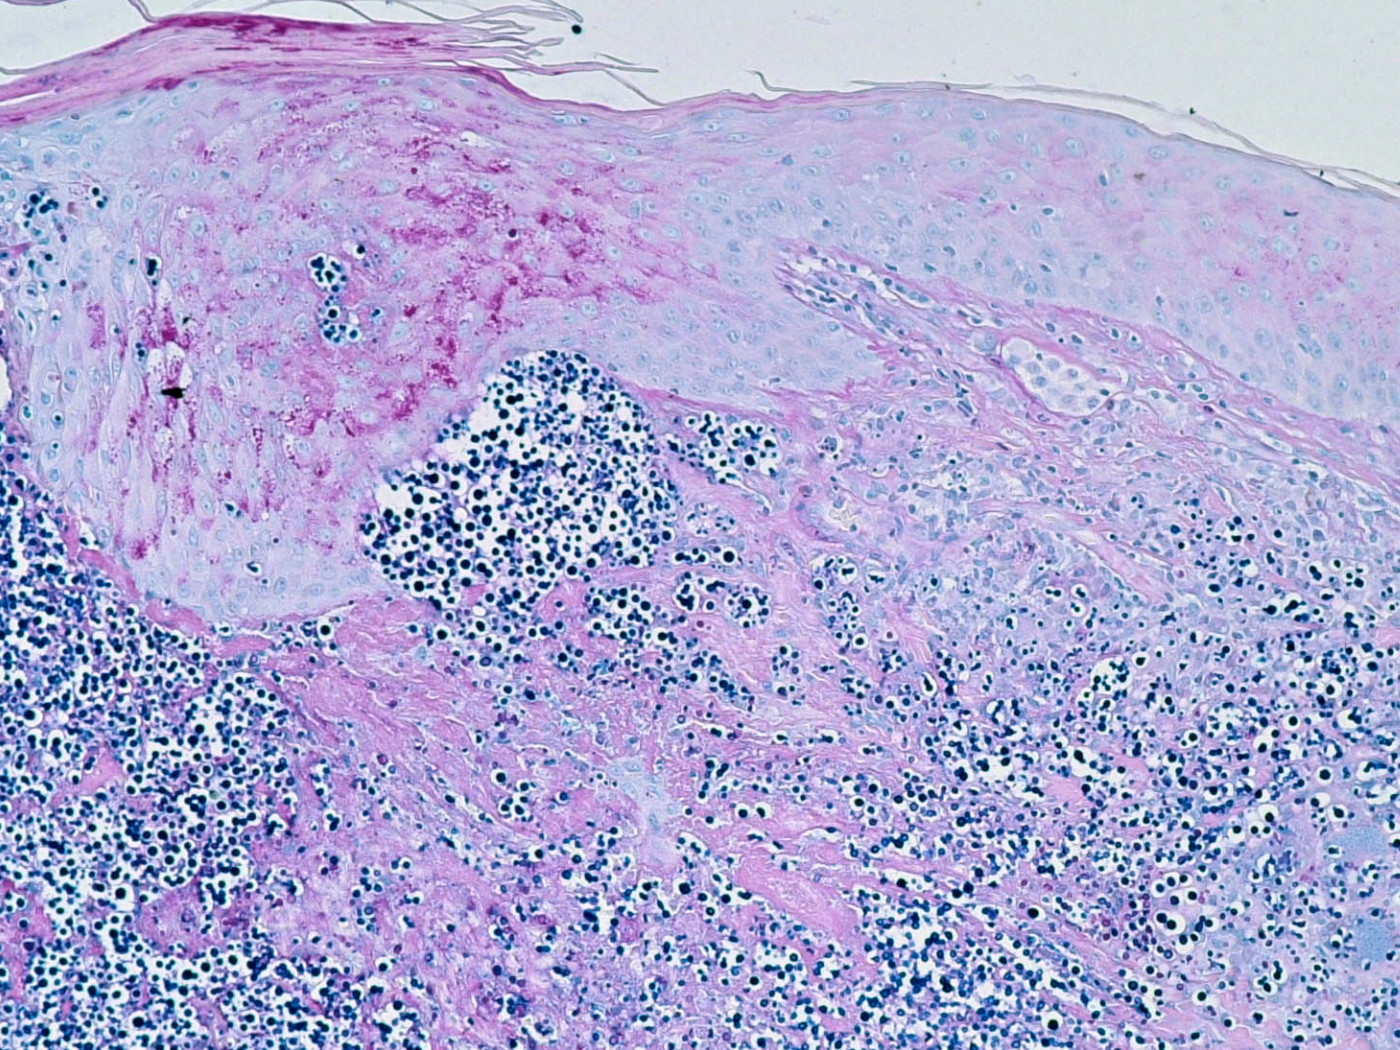

cryptococcen (PA) cryptococcen (PA) Cryptococcus neoformans

PA-foto rechtsonder: Michael Bonert (Nephron) - Wikimedia (Creative Commons License 3.0).

2 biopten van suspecte laesie, voor PA (PAS- of mucikarmijnkleuring) en kweekbiopt. Indien van toepassing aspiraat/vocht opsturen voor kweek. Eventueel pus met 10% KOH bekijken. Gelokaliseerde cutane cryptococcosis zonder systemische infectie is uiterst zeldzaam dus aanvullend onderzoek is nodig: lab (BSE, leuko's + diff, nierfunctie, glucose, alkalische fosfatase, HIV-test, CD4), X-thorax, indien afwijkend: consult longarts (BAL, Percutane longpuntie), kweken van urine (33%), bloed (10%) en sputum (10%), consult neuroloog (lumbaal punctie, directe uitstrijk liquor, glucose, eiwit, leucocyten (lymfocytose), kweek, aantonen kapsel antigeen (90%). Het cryptococcen kapsel antigeen (latex agglutinatie) kan worden bepaald in liquor, serum, en sputum. Cryptococcen antistoffen (IIF) worden gevonden bij 77-90% van de patiënten.